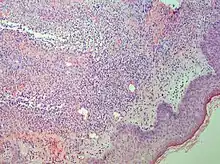

Interface dermatitis with lichenoid inflammation

| Generally/Not otherwise specified | Typical findings:[2]

|

||

| Lichen planus | Irregular epidermal hyperplasia with a jagged “sawtooth” appearance, compact hyperkeratosis or orthokeratosis, foci of wedge-shaped hypergranulosis, basilar vacuolar degeneration, slight spongiosis in the spinous layer, and squamatization. The dermal papillae between the elongated rete ridges are frequently dome shaped. Necrotic keratinocytes can be observed in the basal layer of the epidermis and at the dermal-epidermal junction. Eosinophilic remnants of anucleate apoptotic basal cells may also be found in the dermis and are referred to as “colloid or civatte bodies”. Whickham striae are usually seen in the areas of hypergranulosis. Vacuolar degeneration at the basal layer may be noted leading to focal subepidermal clefts (Max Joseph spaces). Squamatization occurs as a result of maturation and flattening of cells in the basal layer. It happens in areas of marked hypergranulosis with prominence of the sawtooth pattern of rete ridges. Wedge-shaped hypergranulosis can occur in the eccrine ducts (acrosyringia) or hair follicles (acrotrichia). In the hypertrophic subtype, the associated hyperkeratosis, parakeratosis, hypergranulosis, papillomatosis, acanthosis, and hyperplasia markedly increased with thicker collagen bundles forming in the dermis. Moreover, the rete ridges are more elongated and rounded as opposed to the typical sawtooth pattern. In atrophic LP, loss of the rete ridges and dermal fibrosis is prominent. In vesiculobullous LP, the disease progression is quicker. Hence, some of the distinctive features such as hyperkeratosis, hypergranulosis, or dense lymphocytic dermal-epidermal infiltrate may not be present. LP lesion may resolve with residual hyperpigmentation caused by a persistent increase in the number of melanophages in the papillary dermis.[9] | ![]() | ![]() |